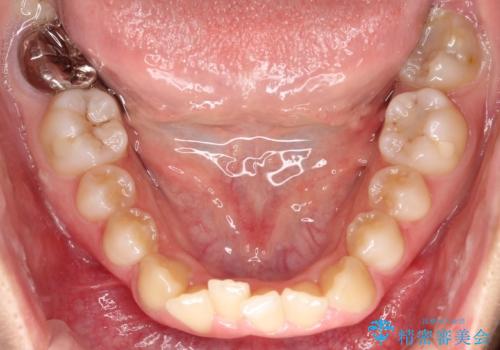

- 前歯のデコボコ(叢生)と、前歯が上下逆の咬み合わせ(反対咬合)を主訴にご来院されました。精密検査の結果、歯列全体のスペースが不足していることが判明。患者様のご希望に合わせ、透明で目立ちにくい**インビザライン(マウスピース矯正)**による治療計画を立案しました。歯を抜かずに、歯列全体を奥(遠心)へ移動させることで、歯が並ぶスペースを確保し、叢生と反対咬合を同時に改善することを目指します。

今回の矯正治療では、透明なマウスピース型の装置インビザラインを使用しました。この装置は目立たず、取り外しが可能なため、食事や歯磨きも普段通り行えます。治療は、緻密な治療計画に基づき、段階的に作製されたマウスピースを交換していくことで、遠心移動という方法で奥歯から徐々に歯列全体を後方へ動かしました。これにより、不足していたスペースを確保し、前歯のデコボコを解消。同時に、上下の歯の前後的な関係を改善することで、反対咬合も正常な咬み合わせへと導きました。見た目も機能も改善し、自然で美しい笑顔を獲得していただけました。